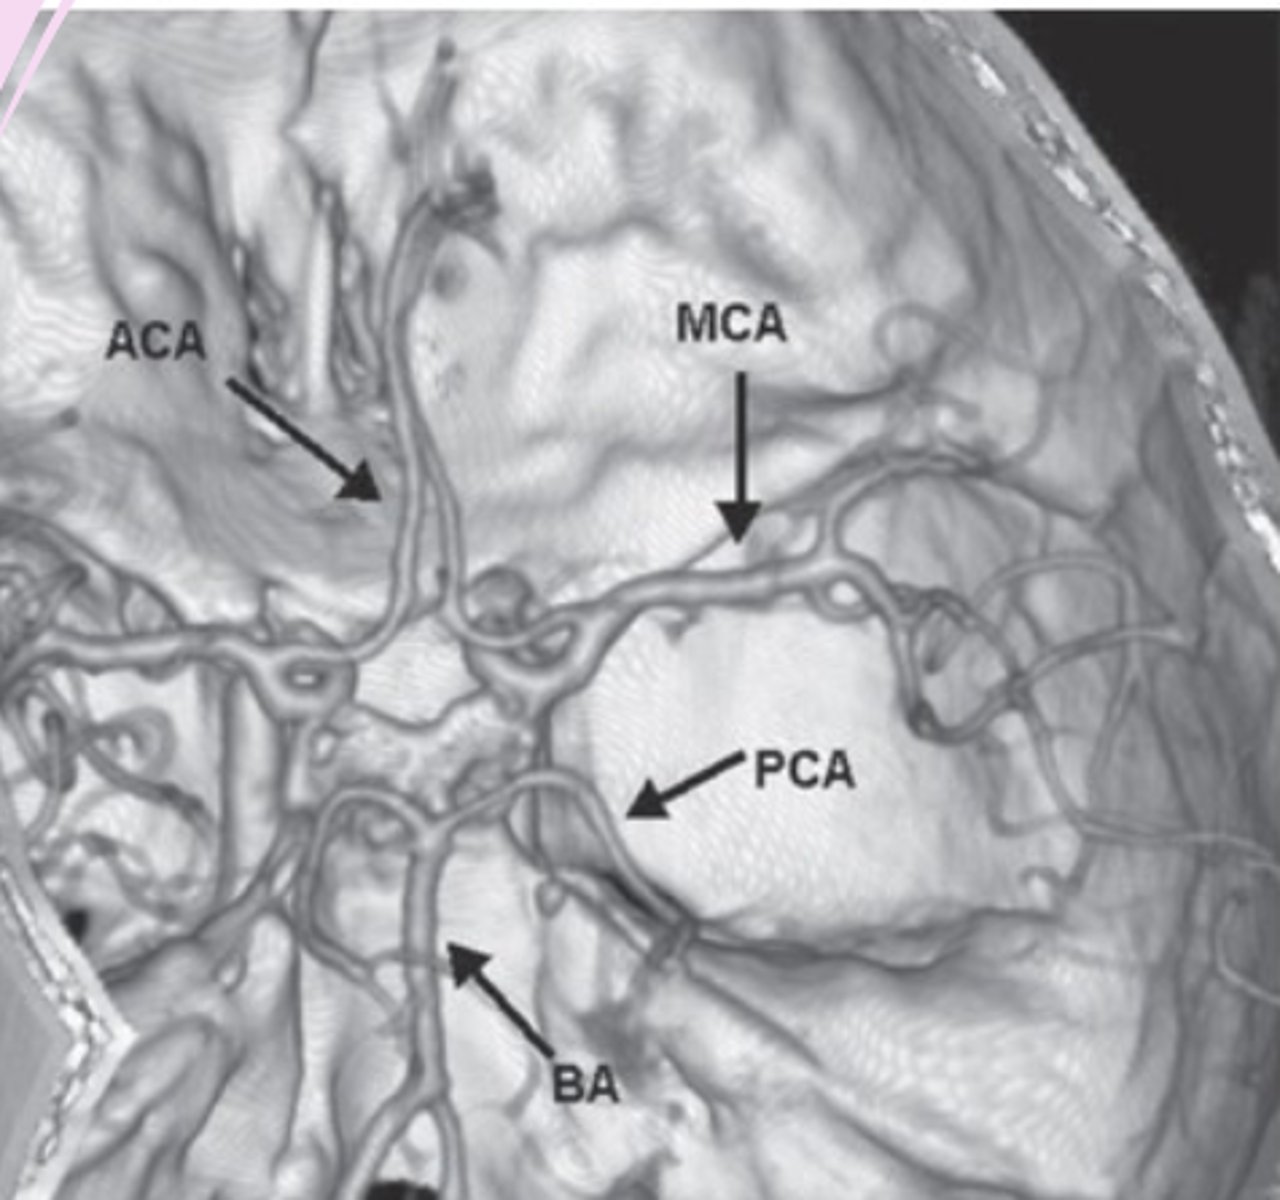

CT angiography (CTA) and MR angiography (MRA)

visualization of vasculature

look for aneurysms, stenosis, occlusion, dissection, vascular irregularities

CT angiography

-order when need to see blood vessels

3D images

safe